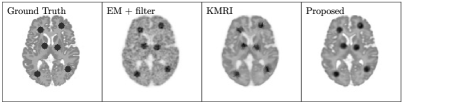

A 3D brain phantom from BrainWeb [31] was used in the simulation. Corresponding T1 weighted MR image was used as the prior image. The voxel size is 2×\times2×\times2 mm3superscriptmm3\mbox{mm}^{3} and the phantom image size is 128×\times128×\times105. To simulate mismatches between the MR and PET images, twelve hot spheres of diameter 16 mm were inserted into the PET image as tumor regions, which are not visible in the MR image. In this experiment, the last 5 min frame of a one-hour FDG scan was used as the ground-truth image. The computer simulation modeled the geometry of a Siemens mCT scanner. Noise-free sinogram data were generated by forward-projecting the ground-truth image using the system matrix and the attenuation map. Poisson noise was then introduced to the noise-free data by setting the total count level to be equivalent to last 5 min scan with 5 mCi injection. Gaussian post-filtering method (denoted as EM+filter) and the kernel method (denoted as KMRI) [12] were employed as comparison methods. Fig. 4 shows three orthogonal views of the reconstructed images using different methods. The kernel method and the proposed method both reveal more cortex structures compared to the EM-plus-filter method due to the boundary information provided by the MR priors. Compared to the kernel method, the proposed method can recover even more details of the cortices and the white matter regions are cleaner. Besides, the tumor uptake using the proposed method is higher and the tumor shape is closer to the ground truth. This means that even when there are mismatches between the PET and MR images, the proposed method can still recover the true PET intensities and shapes. Fig. 6(a,b) shows the contrast recovery coefficient(CRC). vs standard deviation (STD) curves for different methods. For both the gray matter region and the tumor region, the proposed method out-performs other methods.

Figure 4: Three orthogonal slices of reconstructed images using different methods for the simulation brain dataset.

Figure 5: The three rows show three orthogonal slices for the clinical brain dataset using different method. The first column is the corresponding MR prior image.

A 70-minutes dynamic PET scan of a human subject acquired on a Siemens Brain MR-PET scanner after 5 mCi FDG injection was employed in the real data evaluation. The data were reconstructed with an image array of 256×\times256×\times153 and a voxel size of 1.25 ×\times 1.25 ×\times 1.25 mm3superscriptmm3\mbox{mm}^{3}. A simultaneous acquired T1-weighted MR image has the same image array and voxel size as the PET images. Correction factors for attenuation, randoms, scatters were estimated using the standard software provided by the manufacturer and included during reconstruction. The motion correction was performed in the LOR space based on the simultaneously acquired MR navigator signal[32]. To generate multiple realizations for quantitative analysis, the last 40 minutes PET data were binned together and resampled with a 1/8 ratio to obtain 20 i.i.d. datasets that mimic 5-minutes frames. As the ground truth of the regional uptake is unknown, a hot sphere with diameter 12.5 mm, mimicking a tumor, was added to the PET data (invisible in the MRI image). For tumor quantification, images with and without the inserted tumor were reconstructed and the difference was taken to obtain the tumor only image and compared with the ground truth. The tumor contrast recovery (CR) was calculated as CR=1/Rr=1Rl¯r/ltrueCR1𝑅superscriptsubscript𝑟1𝑅subscript¯𝑙𝑟subscript𝑙true{\text{CR}=1/R\sum\nolimits_{r=1}^{R}\bar{l}_{r}/{l}_{\text{true}}}, where l¯rsubscript¯𝑙𝑟\bar{l}_{r} is the mean tumor uptake inside the tumor ROI, ltruesubscript𝑙true{l}_{\text{true}} is the ground truth of the tumor uptake, and R𝑅R is the number of the realizations. For the background, 11 circular ROIs with a diameter of 12.5 mm were drawn in the white matter to calculate the standard deviation. Fig. 5 shows the reconstructed images and the corresponding MR prior images of the real brain dataset using different methods. For the methods with MR information included, more cortex details are recovered and the image noise in the white matter is much reduced. The cortex shape in the proposed method is clearer than the kernel method. For the tumor region which is unobserved in the MR image, the uptake is higher in the proposed method compared with the kernel method. Fig. 6(c) shows the CR-STD curves for different methods. Clearly the proposed method has the best CR-STD trade-off compared with other methods.